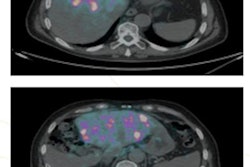

The new journal will feature articles on hybrid and multimodality imaging in clinical practice and trials as well as preclinical research, according to Editor-in-Chief Dr. Arturo Chiti, who is also a member of the editorial advisory board of AuntMinnieEurope.com. The journal currently is seeking articles for consideration and submission.